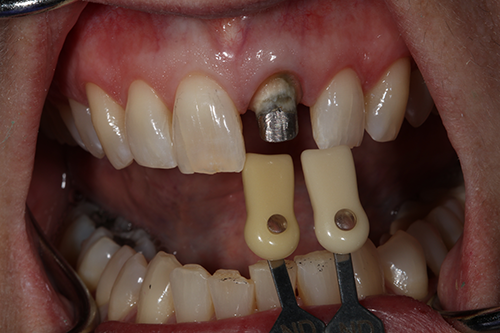

A 60-year-old female presented upon referral from her general dentist for prosthodontic treatment when she requested a new full-coverage crown restoration for tooth #9. She fractured the tooth participating in gymnastics as a child. The tooth was initially restored with composite resin, but when it became discolored, endodontic therapy followed by placement of a cast post, core and crown was performed. The ceramic on the mesial-incisal portion of the crown had fractured (Fig. 1), so the patient reported that it was finally time to replace it.

Fig. 1 Fig. 2

The patient also reported that she was never happy with the restoration, and she also was unhappy with the incisal chipping on tooth #8. Since she was about to embark on a new career, she wanted a smile she felt confident about.